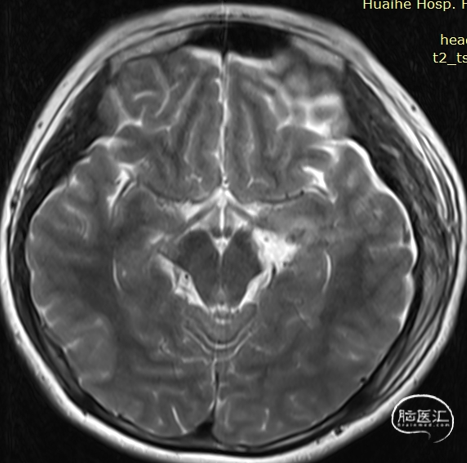

术前检查

术前影像:

左侧海马旁回海绵状血管瘤。